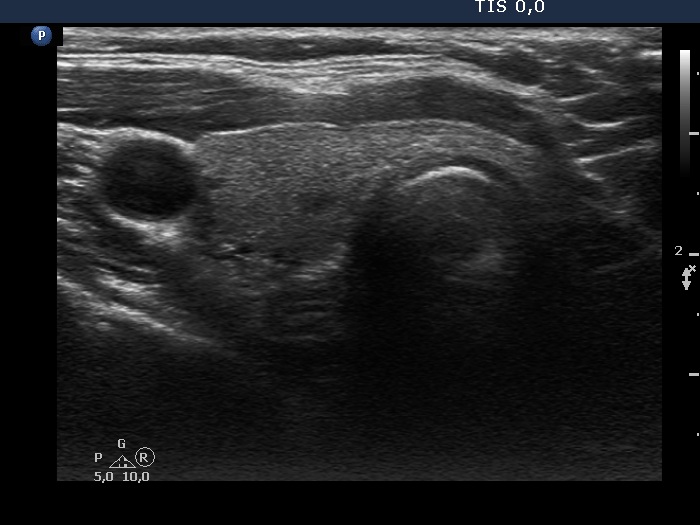

Ultrasonography. The thyroid was echonormal and presented several discrete lesions, most had no significance. The only possible relevant lesion was a minimally-moderately hypoechogenic nodule in the lower third of the left lobe.